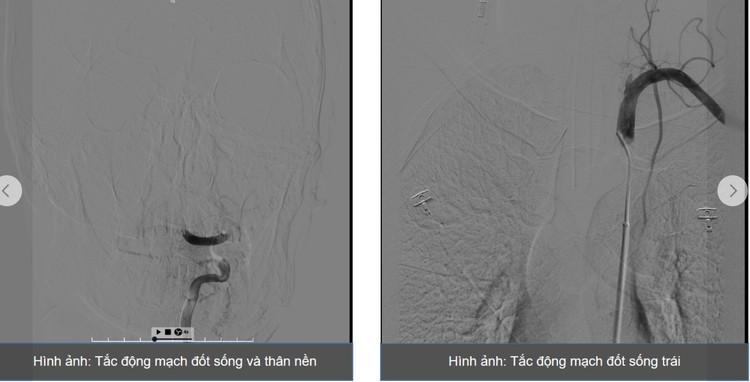

ThS.BS Giáp Hùng Mạnh – Trưởng khoa Thần kinh, Vật lý trị liệu – Phục hồi chức năng, Bệnh viện Bãi Cháy cùng ê-kíp đã tiến hành chụp mạch não, phát hiện tắc gốc động mạch đốt sống trái, trong khi động mạch đốt sống phải có kích thước nhỏ.

Ê-kíp quyết định hút huyết khối tại vị trí tắc, tái lập một phần dòng máu lưu thông nhưng phát hiện hẹp nặng gốc động mạch đốt sống trái. Các bác sĩ tiếp tục nong bóng và đưa ống hút chuyên dụng qua vị trí hẹp.

Sau can thiệp, hình ảnh chụp mạch cho thấy tắc động mạch đốt sống đoạn trên và thân nền. Ê-kíp tiếp tục hút huyết khối và bơm thuốc tiêu sợi huyết tại chỗ. Sau khoảng 10 phút, chụp kiểm tra cho thấy mạch máu được tái thông hoàn toàn.